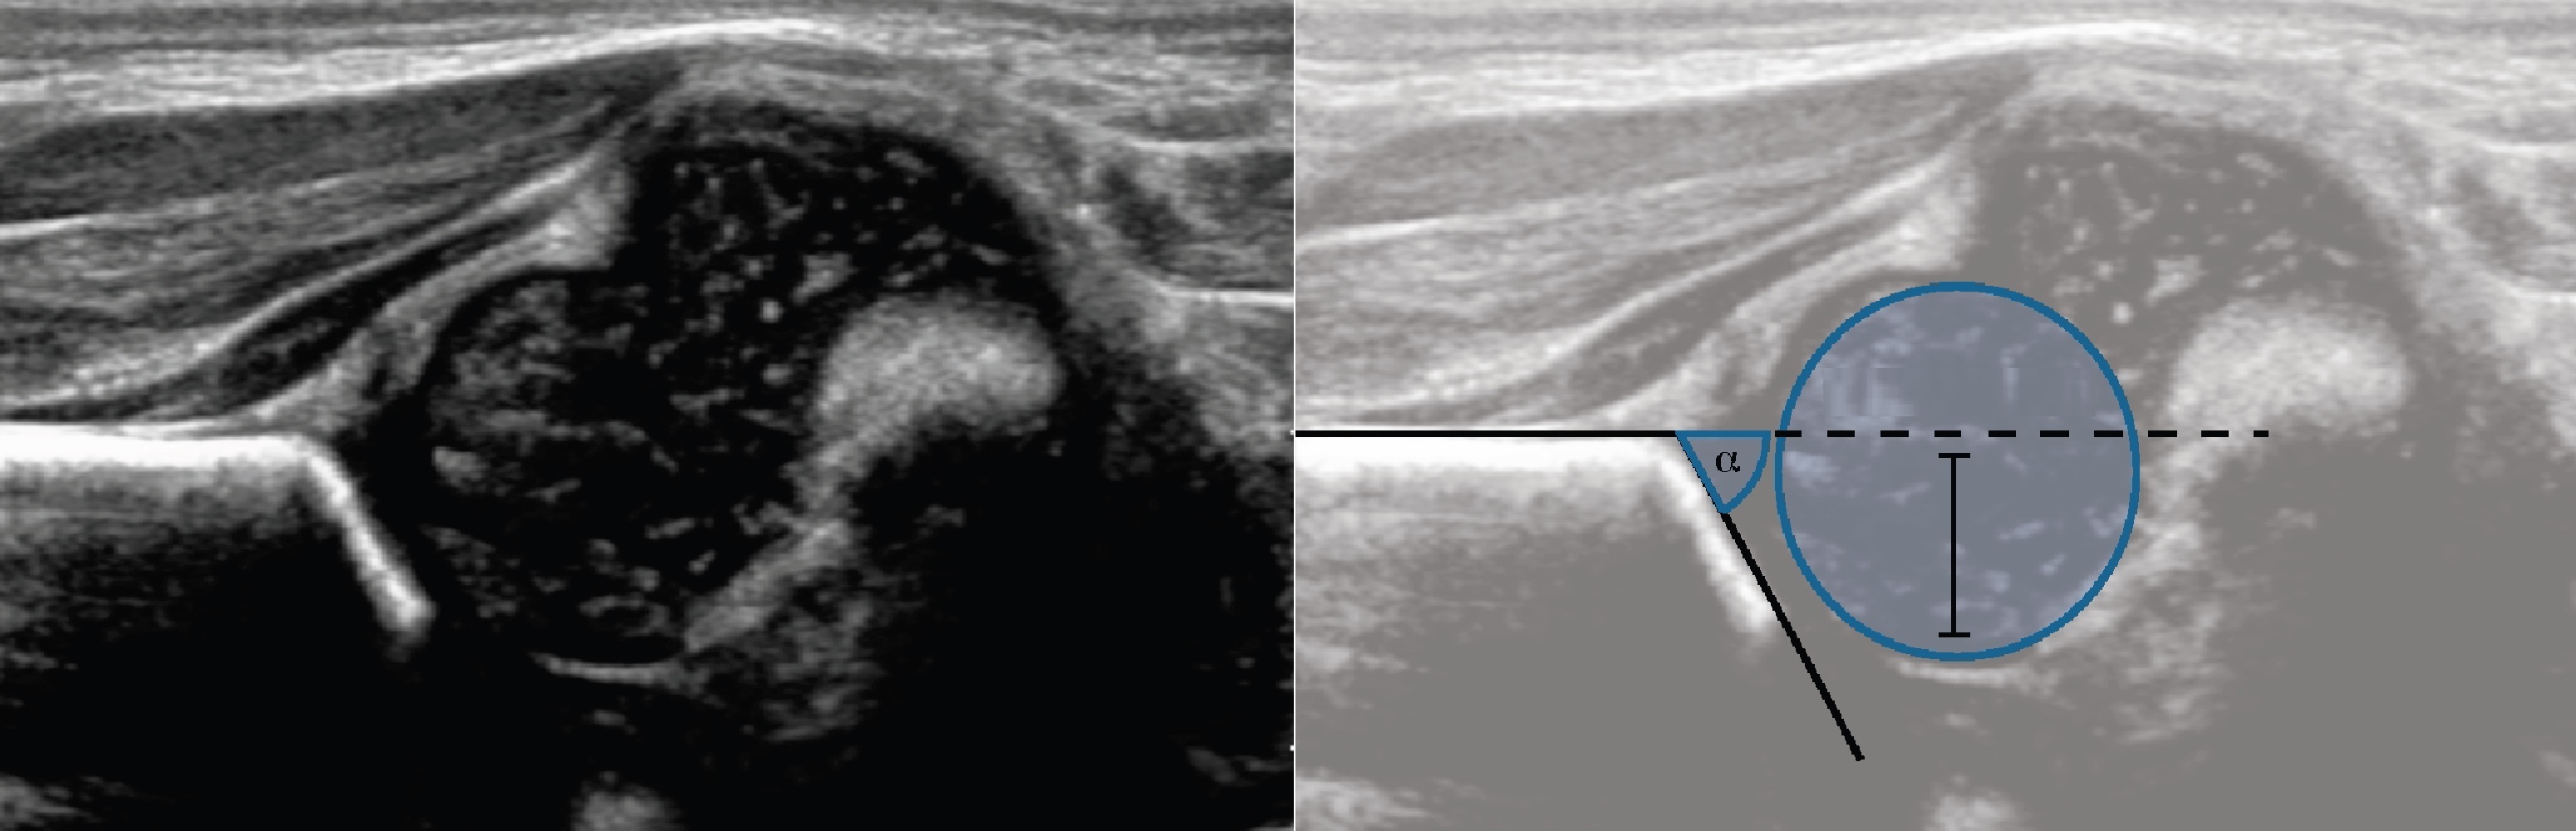

Узи Тазобедренного Сустава Фото 117 фотографий